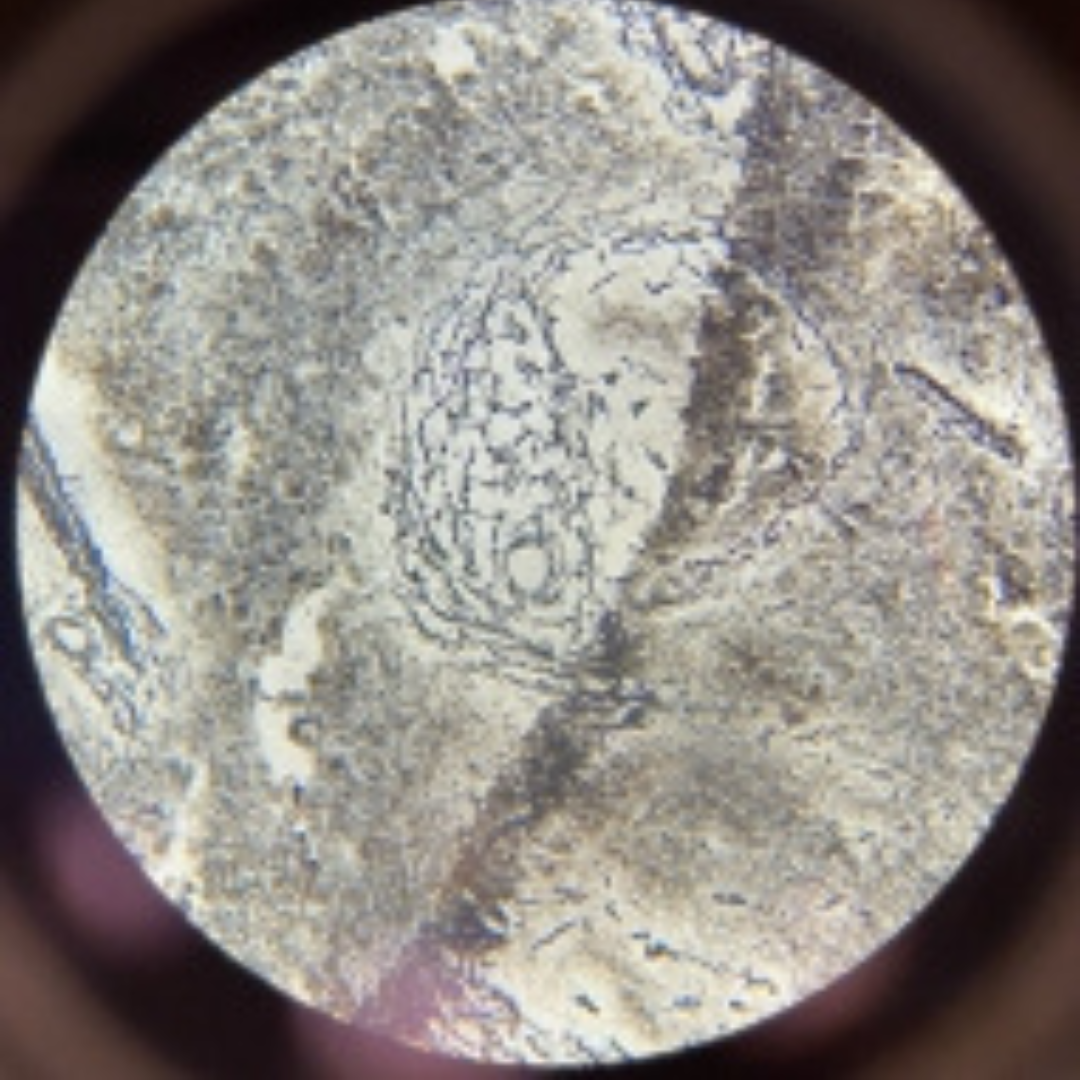

New cards

Thymus (Involuted)

30

New cards

Thymus (Involuted)

31

New cards

Thymus (Involuted)

32

New cards

Thymus